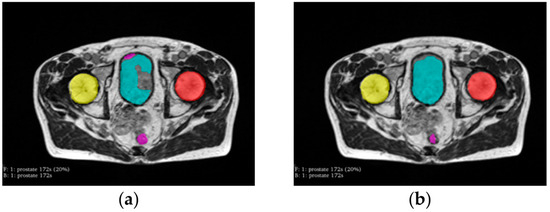

2.2. Preprocessing

2.4. Post-Processing